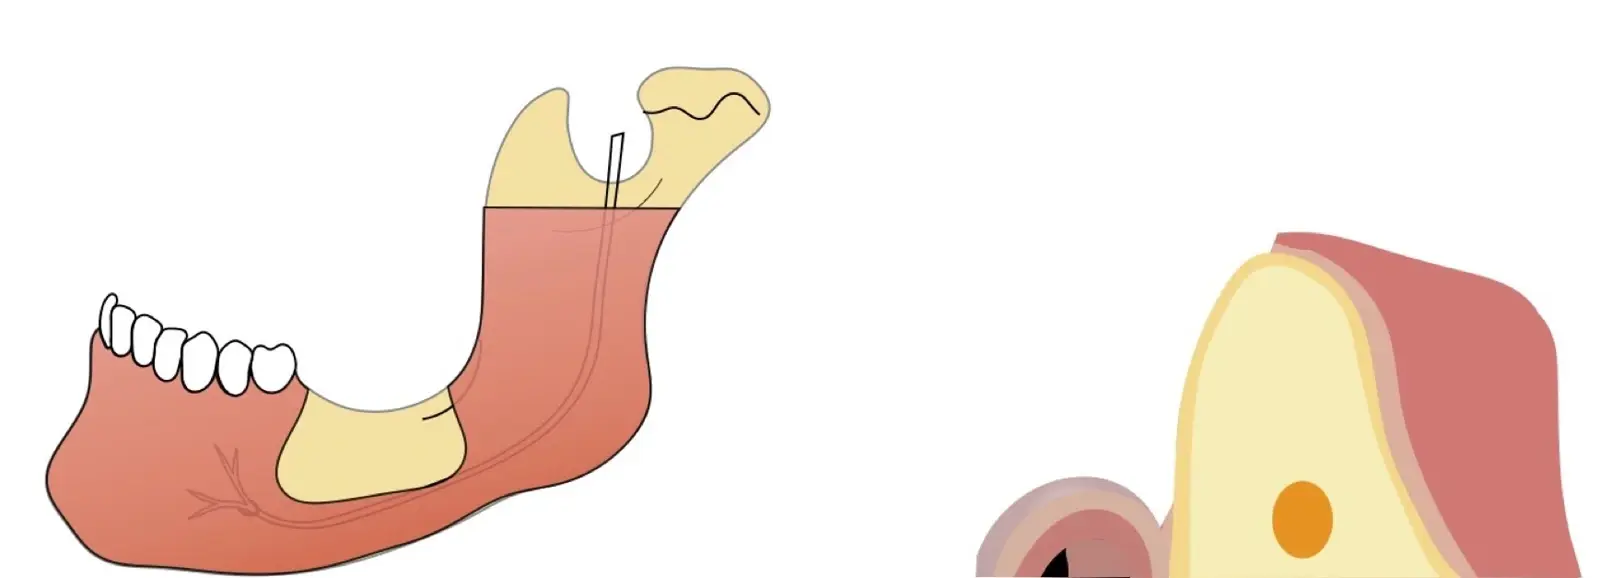

Figura 1. Evaluación clínica: zona donadora (a) y zona receptora (b).

Si la zona donadora es la sínfisis mentoniana, se deben tomar en cuenta los límites de seguridad para la extracción del injerto, que son 5 mm alejado de los ápices, y 5 mm alejado del agujero mentoniano (Figuras 2 y 3).